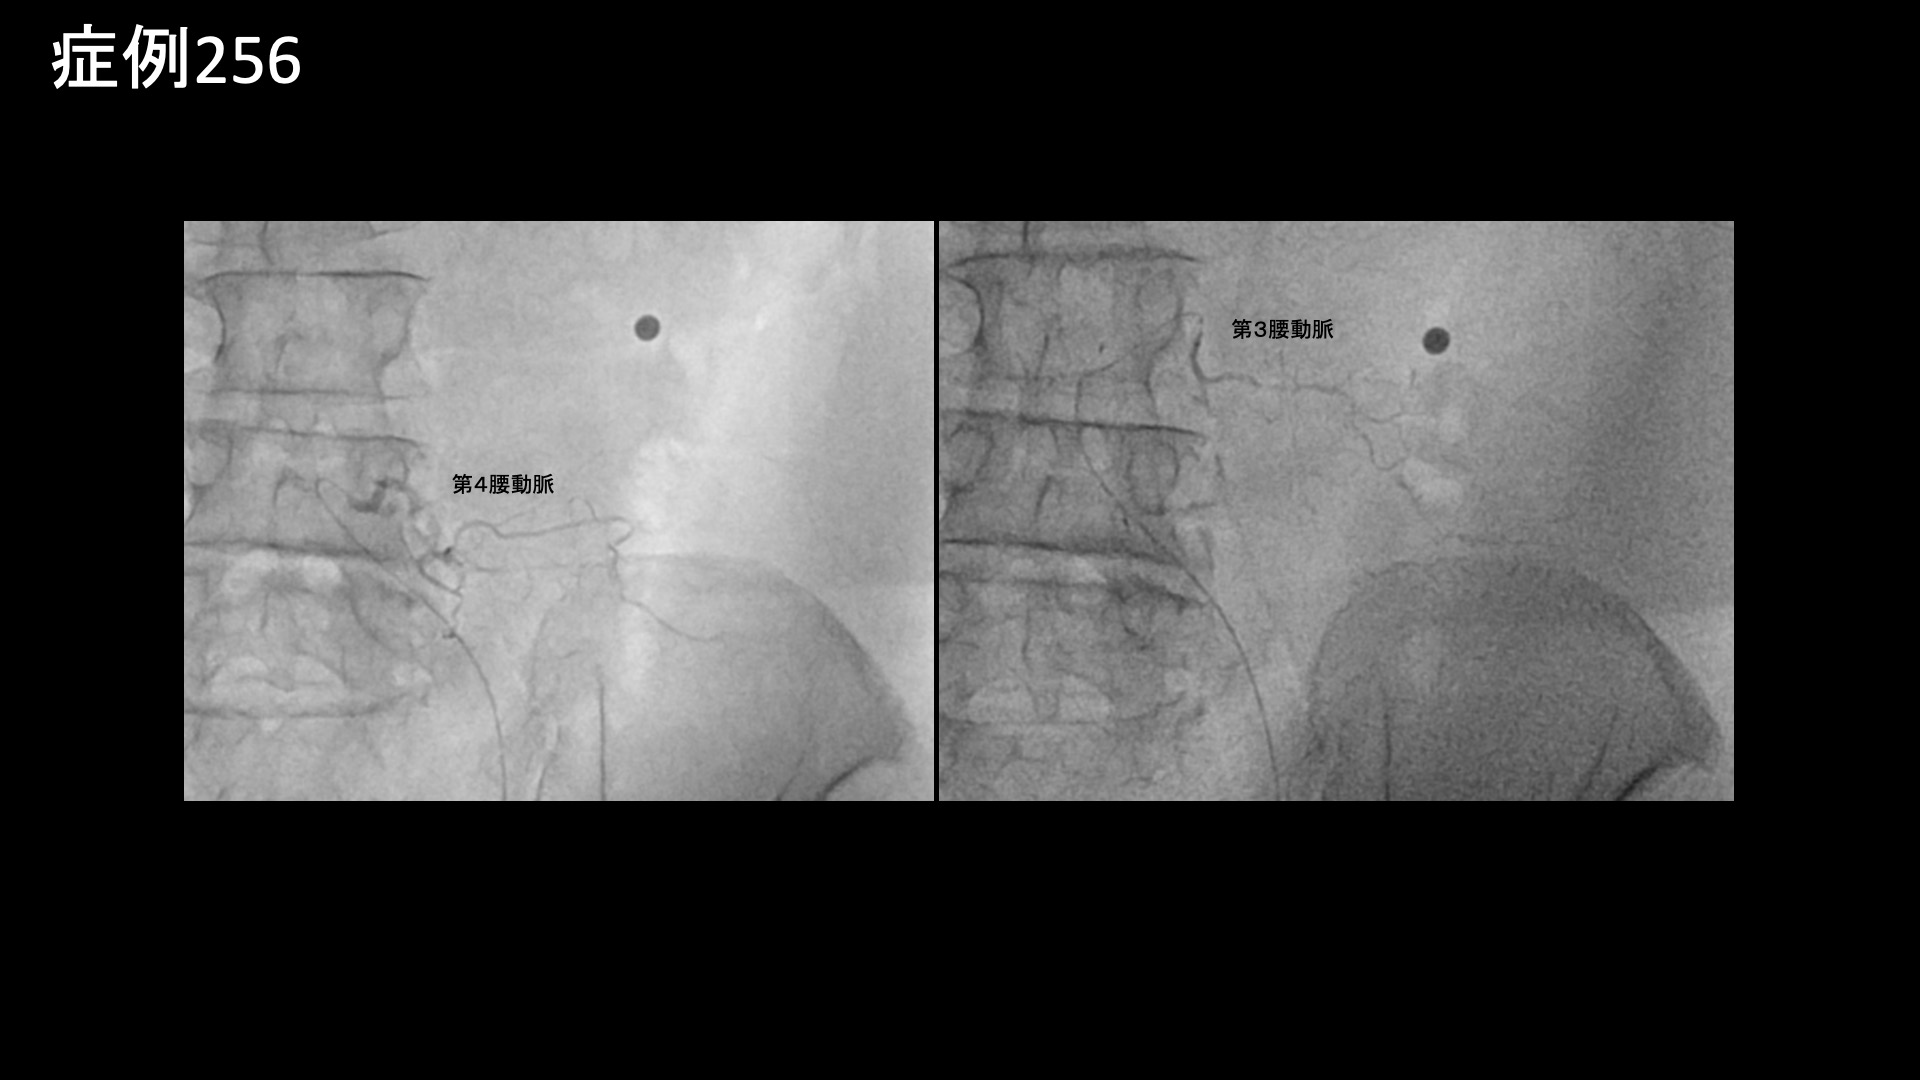

腰:椎間関節炎など 【60代:男性】15年前からの慢性腰痛が急激に悪化して夜も寝られず・・ヘルニアは悪さをしていないなら原因は?(筋・筋膜性疼痛症候群、仙腸関節障害、腰椎椎間板ヘルニア) 2025.12.23 鴨井院長による動画解説 受診までの経過 15年前から慢性的に腰痛がありました。1年前にひどい痛みと脱力に襲われ、MRI検査を受けたところ、腰椎椎間板ヘルニアと診断されました。手術も検討していましたが、自然軽快し、再び歩けるようになりました。しかしながら、右側の腰痛は軽快したものの、左側の強い腰痛が残っていました。ヘルニアで強く圧迫されていたのは右側の神経であったため、整形外科では首を傾げられました。じっとしていると増悪し、長時間の立位でも増悪しました。そのため、夜痛みで寝られないことが多く、起床後も11時くらいになってようやく動けるようになる状態でした。 *50年前に腸骨骨折の既往あり 診察時の所見 MRI検査を確認すると、やはりヘルニアで圧迫を受けているのは右側であり、ヘルニア所見と症状は合致しませんでした。腰の可動域をチェックすると。すべてに動作において中等度の制限がありました。股関節の内外旋動作では可動域は保たれているものの、動きに抵抗があり比較的高度の硬さがありました。触診では、第2―4腰椎レベルでは左腰部の筋肉部において有意に圧痛が認められました。レントゲンでは、左上前腸骨棘を中心に腸骨に骨表層不整像や骨硬化像が見られており、同部位に付着する腸骨筋、縫工筋、大腿筋膜張筋が関与する筋・筋膜性の障害が示唆されました。いずれも股関節の動きに関与する筋肉です。腸骨にはほかに腸腰筋や臀筋が関与し、いずれも腰臀部痛の原因として重要です。こうした腸骨の変化や、筋硬直、その他の特徴的な身体所見から総合的に判断して、筋・筋膜性疼痛症候群を主体として、仙腸関節障害も合併している状態と判断しました。骨盤の不安定性が一因ですので、腸骨骨折の既往とも関係があるかもしれません。以上より治療適応と判断し、モヤモヤ血管(病的新生血管)に対する運動器カテーテル治療(微細動脈塞栓術)を受けていただきました。 治療の所見 第2腰動脈~第4腰動脈の筋肉枝を選択的に治療し、さらに、腰痛の主要責任血管の一つである腸腰動脈や外側仙骨動脈、臀筋群に関与する上殿動脈、下殿動脈、股関節の動きにも関わる閉鎖動脈やその他の筋肉枝など複数個所の治療を広範囲に行いました。 治療後の経過 治療後2週間、まだ大きな変化はないものの、痛みが少しましになったほか、寝られる日が多くなってきました(以前は痛みで寝られないことが多かった)。治療後1ヶ月半、時々痛むことはあるものの、だいぶ良くなってきました。痛みで寝られないということは無くなりました。『本当に寝られなくて辛かったので嬉しい、何十歳か若返ったように思う』と大変喜ばれました。まだ左腰部に1か所だけ、塊のように感じる部分が残っているものの、それもだいぶ柔らかくなりました。治療後3ヶ月、塊の部分はやはり一定の違和感があるものの、痛みは感じなくなりました。全体的には疲れると疼くように痛むことがあるものの、元の7割程度の痛みは解消されました(3/10程度に改善)。夜寝られないほどの腰痛というのはかなり重症度が高いわけですが、これほどの状態であっても、MRIで原因がわからないことは珍しくありません。丹念に診察をして原因を見つけ出し、治療を行うのが痛み治療専門医師の腕の見せ所ですが、良い結果が得られて本当に良かったです。残存症状については追加カテーテル治療が有効ですが、生活習慣の改善や運動療法を地道に行っていくことでさらなる緩和が期待できます。引き続きしっかりとサポートしていきたいと思います。 本症例では、とにかく体の硬さや筋硬直が根底にありました。こうした状態では、腰痛はほぼ必発です。骨格のほか、運動不足や、過剰なトレーニング、急激な体重変動、加齢などが原因です。懸念のある方は、発症予防、再発予防のために硬さの解消に取り組んでください。原因により対処方法は異なりますが、日常的に軽めの運動を取り入れることはいずれの場合も有効です。 筋・筋膜性疼痛症候群の詳細はこちら 【70代:男性】頭痛、こめかみ・眉上の痛み、耳鳴り~頭部顔面の帯状疱疹後遺症に対するモヤモヤ血管治療(帯状疱疹後遺症) 前の記事 【50代:女性】8年前からの両膝・両足首の痛みに加えて踵まで痛み平地歩行もままならず・・進行性の変形性膝関節症および足関節症、足底筋膜炎の合併例に対して2回の運動器カテーテル治療を行った症例(変形性膝関節症、変形性足関節症、足底筋膜炎、肥満) 次の記事